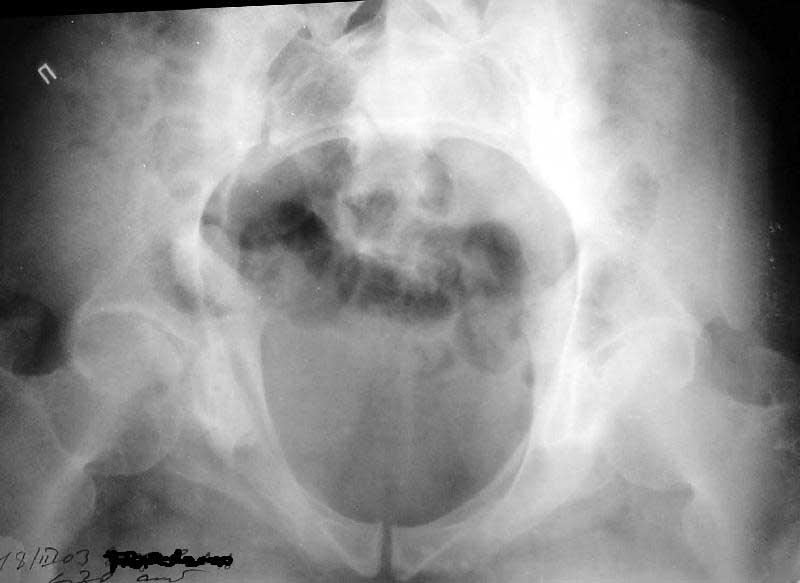

Больной 64 лет, работник тяжелого физического труда, 29.10.02 на производстве получил удар трубой по переднему отделу таза. 2 месяца постельного режима, с 4 месяцев ходит с тростью. Беспокоят тянущие боли в нижних конечнстях при нагрузке, периодически ночные боли, хромота, постоянно припимает анальгетики. Снимки прилагаются. Виден подвывих в правом крестцово-подвздошном сочленении. Как лучше помочь пациенту? Заранее спасибо.